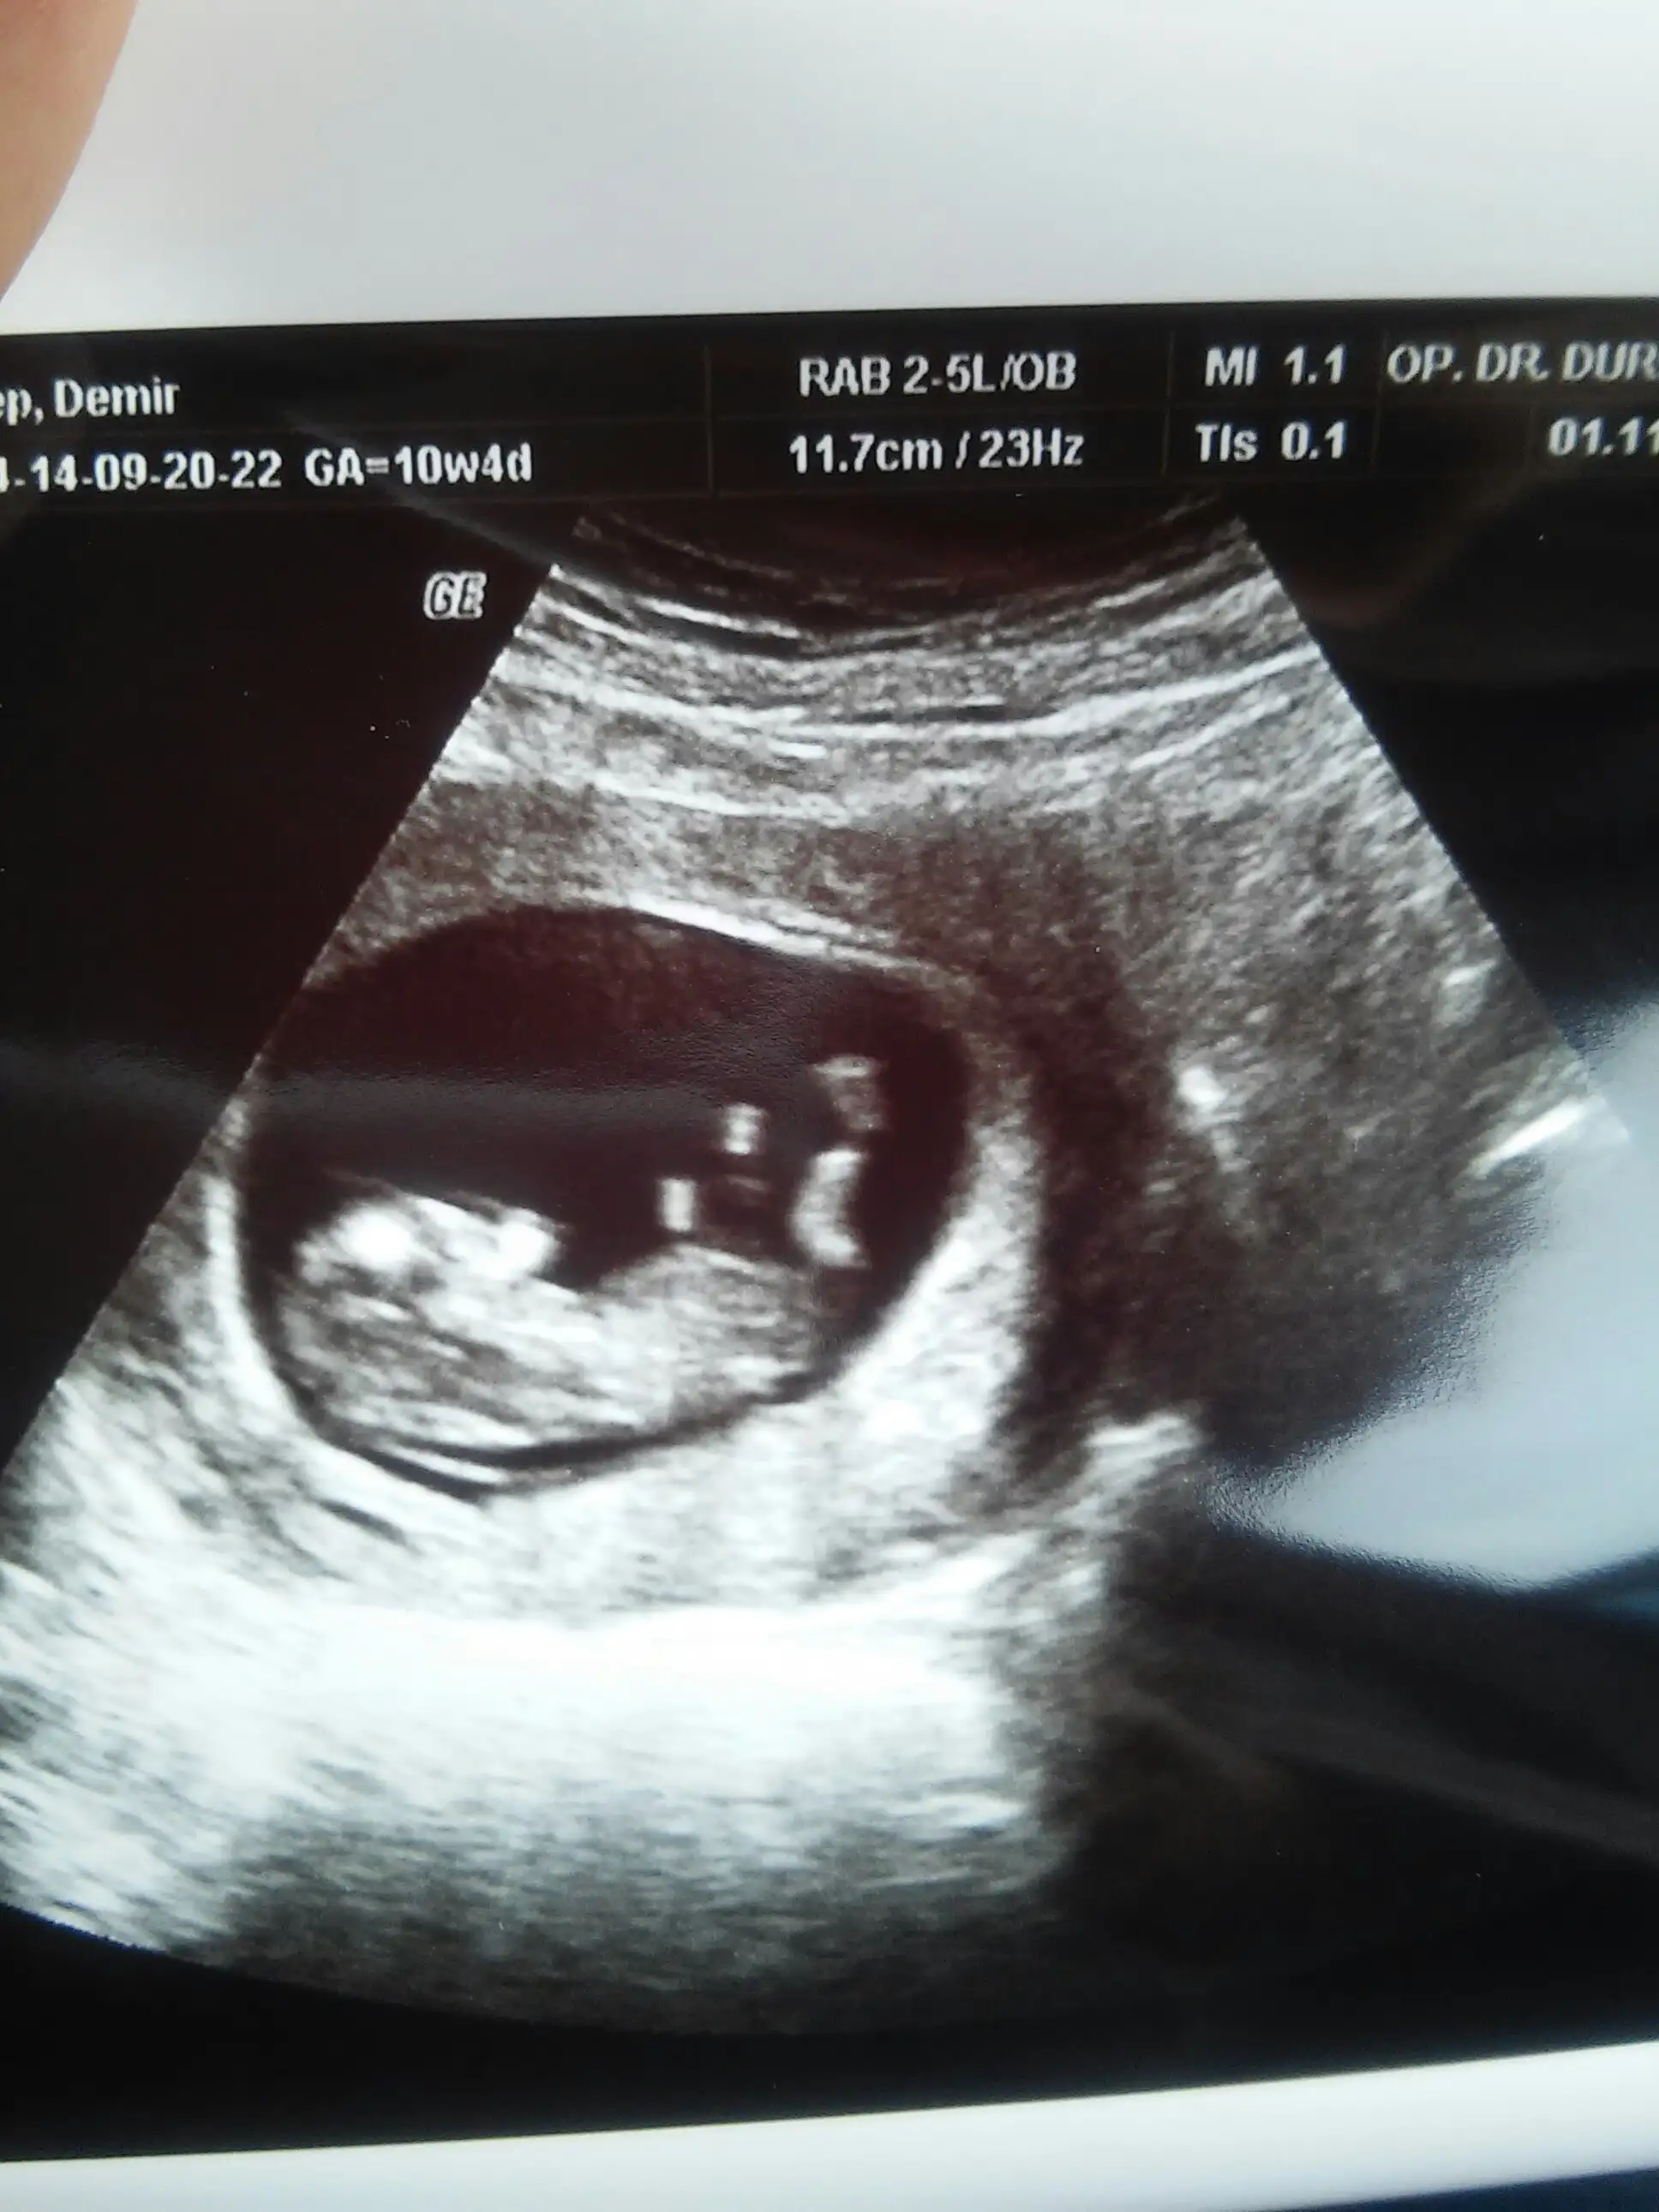

...Banada yorum yaparmisiniz lutfennn 12 haftalik hamileyim bu ultrason görüntüsünde..Eki Görüntüle 1289119